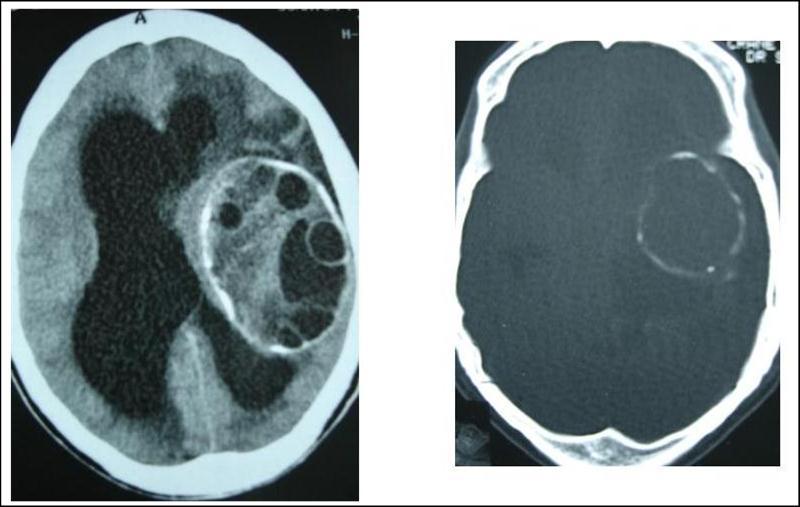

A 27 years-old male patient was admitted with 1 month history of headache, fever, short term memory lack, aphasia, right hemiparesis and seizures. He had liver hydatid cysts excised 8 years before and was treated with adjuvant medication (albendazole). The neurological examination revealed right central third cranial nerve palsy and hemi paresis, with Babinski sign positive, aphasia and papilledema on ocular fundus. The Glasgow Coma Scale was evaluated to 10/15 (E:3; V:1; M:6). A brain CT scan showed a large left temporoparietal intracerebral multiple and calcified hydatid cysts, important mass effect with midline shift about 7 mm following by an obstructive hydrocephalus (Figure 1). Other cysts were found in thalamic region (Figure 2). The Thoraco-abdominal CT scan showed multiple intra peritoneal hydatid cysts (Figure 3). A left temporo parietal craniotomy was performed in emergency. After corticectomy, using Arana-Iniguez technique, the appearance of the capsule suggested infected hydatid cysts with a purulent material which was aspirated. Numerous hydatid cysts were lifted away and several daughter vesicles were carefully removed without rupture (Figure 4). Macroscopically, the abscess wall appeared to be thick, calcified and tightly attached to lateral ventricular, so it could not be removed. The deep cyst overlying the third ventricle was left.in place. Microscopic examination demonstrated live scoleces, protoscoleces and multiple hooks. These findings are consistent with hydatid cyst (granulosis ecchinococcus) (Figure 5). Bacteriology examination found several white blood cells in the pus (neutrophilia) and infection by streptococcus pneumonia. This was consistent with infection. After surgery, the patient had medication (albendazole, specific antibiotherapy and phenobarbital). The inflammation assessment in the blood showed leukocytosis, a high C-reactive protein rate and increased erythrocyte sedimentation rate. Post operative CT scan was performed and showed the residual calcified capsule and decreased ventricular size (Figure 6). Clinical improvement was achieved after treatment. One month after the initial diagnosis, CT scan of the brain showed no recurrence and a physical examination revealed a neurologically intact, fully functional patient and eyes fundus normal. He was discharged and went to abdominal surgery two months later with complete intra abdominal cysts removal. Albendazole treatment was continuing for six months and radiological exploration was performed by brain MRI with spectroscopy at three and six month later. This showed that infection had resolved and the deep cyst overlying the third ventricle is less spherical (Figure 7, Figure 8). Four years later, the outcome was good.

Figure 1.axial CT scans of brain showing multiple hydatid cysts (A) with calcified capsule (B).

Figure 2.axial CT showing another cyst located in thalamic region